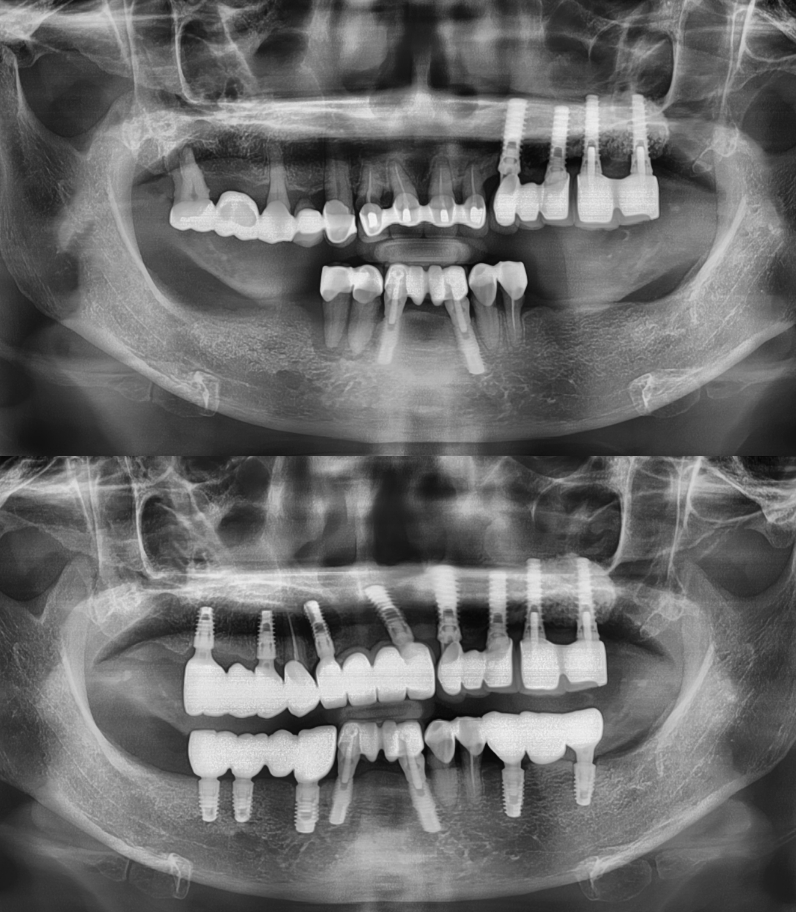

임플란트 전/후

실제 케이스

성공적인 임플란트 치료는 세밀한 분석과

그에 맞는 치료가 중요하기에

다수의 치료 경험을

보유한 의료진이 상주한 곳에서 시작하시기 바랍니다.

임플란트

환자 성함 : 강**

치료기간 : 2023.05 - 2023.12 (7개월)